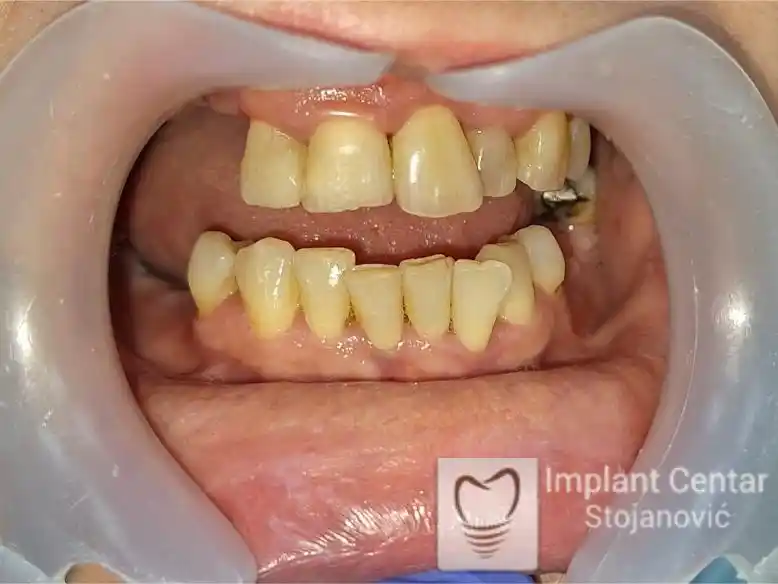

Na slikama 1, 2, 3 , 4  i  5 prikazan je izgled pacijenta pre početka terapije. Nakon detaljne kliničke i radiološke analize, doneta je odluka o vađenju zuba loše biološke vrednosti, dok su bezuba polja sanirana ugradnjom dentalnih implantata.

Nakon ugradnje implantata i pripreme preostalih zuba, pacijentu su izrađene fiksne privremene krunice, čime je postignut eugnatan zagriz već nakon jednog dana (slika 8, 9 i 10). Tokom perioda osteointegracije, pacijent se postepeno privikavao na novi položaj vilica i zagriz.